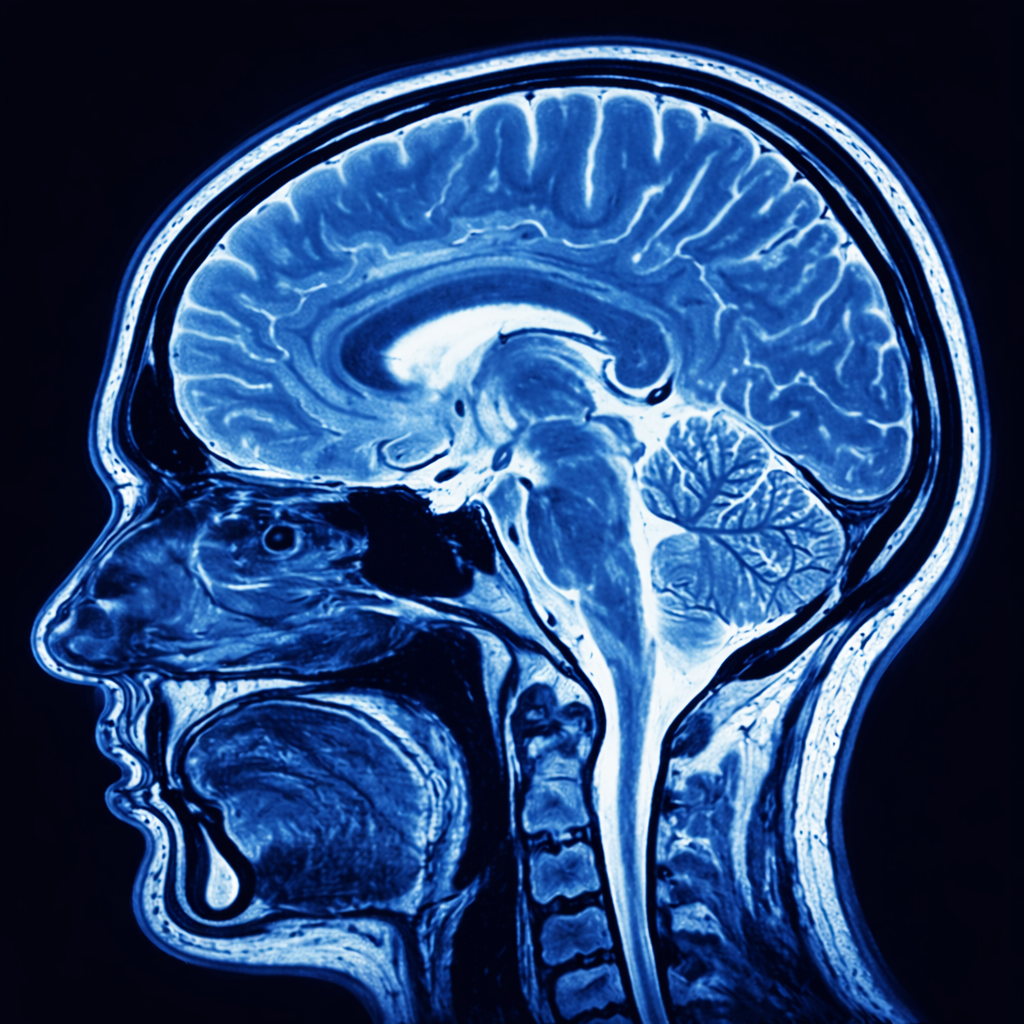

Myndspan provides MRI-based brain health scans that compare an individual's brain structure with large reference datasets to identify patterns linked to attention, mood, and cognitive ageing. These scans are designed to help people understand how their brain differs from typical patterns and can support earlier and more personalised conversations about mental health, cognitive function, and brain-based regulation differences.